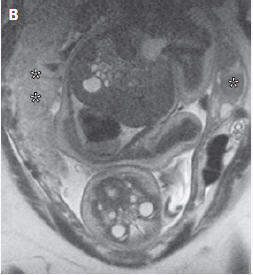

1855年5月3日

第一例子宫切除术被报道。患者是一名34岁的子宫肌瘤患者,在每次月经来临时都会有致命性的出血。作者称子宫切除手术是"最后的办法"(a last resort)。